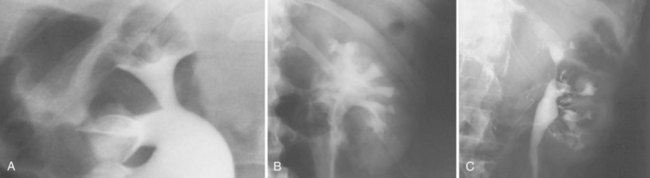

Backflow occurs during retrograde pyelography when contrast is injected under pressure and escapes the collecting system. Contrast may escape the collecting system by one of four routes: Pyelotubular backflow occurs when contrast fills the distal collecting ducts producing opacification of the medullary pyramids (Fig. 4–7A). Pyelosinus backflow occurs when a tear in the calyces at the fornix allows contrast to leak into the renal sinus (Fig. 4–7B). Pyelolymphatic backflow is characterized by opacification of the renal lymphatic channels (Fig. 4–7C). Pyelovenous backflow is seen when contrast enters the venous system, resulting in visualization of the renal vein.

Figure 4–7 Patterns of backflow during retrograde pyelography. A, Pyelotubular backflow. B, Pyelosinus backflow. C, Pyelolymphatic backflow.